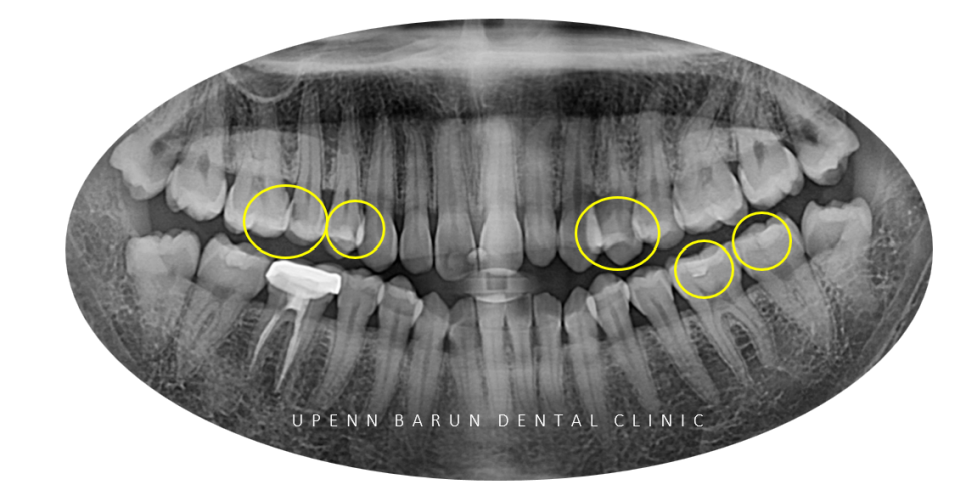

21/4

교정을 시작하기에 앞서

엑스레이를 확인해보니

이전에 충치치료를 받으신 곳이 여럿 보이고,

충치가 많이 생긴 상태였어요 T^T

엑스레이에 눈에 띄게 충치치료가 필요한 상황으로

보존적인 치료를 위해

레진치료의 장인 이기도 하신

김승우 원장님께서는 부위별로 충치치료를 진행해주셨습니다! ^^